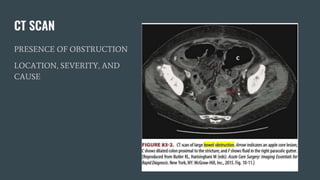

CT SCAN

PRESENCE OF OBSTRUCTION

LOCATION, SEVERITY, AND

CAUSE

CT SCAN PRESENCE OFOBSTRUCTION LOCATION, SEVERITY, AND CAUSE